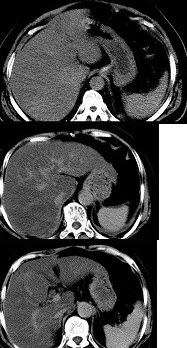

男,32岁,肥胖,常酗酒,肝肋下一横指,肝区轻微压痛,影像表现如图,应诊断为( )

A:肝炎

B:肝硬化

C:脂肪肝

D:肝豆状核变性

E:肝含铁血黄素沉着